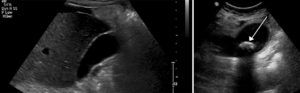

Lijevo: uredan UZV prikaz žučnog mjehura. Desno: kamenac unutar žučnog mjehura.

Osim fizikalnim pregledom, koji otkriva bolnost u gornjem desnom dijelu trbuha, žučni kamenci se dijagnosticiraju krvnim pretragama i ultrazvučnim pretragama, pri čemu je prednost ultrazvuka ta, što s 99% točnošću otkriva žučne kamence promjera svega 2 mm.